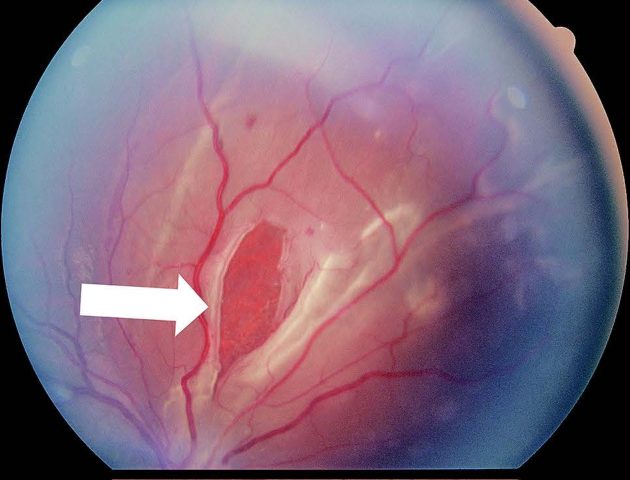

網膜剥離は、多くの場合、網膜に裂け目(網膜裂孔)ができ、そこから網膜が内側にはがれてしまうことで起こります。初期症状としては、糸くずや小さな虫のような影が見える飛蚊症や、暗い場所で光が走るように感じる光視症が見られることがあります。放置すると網膜剥離が広がり、視野が欠けたり、急激な視力低下をきたしたり、失明に至ることもあるため、早期の発見と治療が重要です。

網膜剥離は、多くの場合、網膜に裂け目(網膜裂孔)ができ、そこから網膜が内側にはがれてしまうことで起こります。初期症状としては、糸くずや小さな虫のような影が見える飛蚊症や、暗い場所で光が走るように感じる光視症が見られることがあります。放置すると網膜剥離が広がり、視野が欠けたり、急激な視力低下をきたしたり、失明に至ることもあるため、早期の発見と治療が重要です。